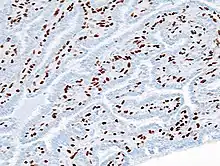

| _p63.JPG.webp) | |

| Histopathology of intraductal papilloma of the breast by excisional biopsy. Immunostaining for p63 protein. | |